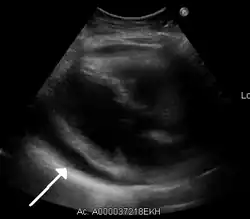

-

Ultrasounds showing a pericardial effusion in someone with pericarditis

A pericardial effusion as seen on CXR in someone with pericarditis

The diagnosis of tamponade can be confirmed with trans-thoracic echocardiography (TTE), which should show a large pericardial effusion and diastolic collapse of the right ventricle and right atrium. Chest X-ray usually shows an enlarged cardiac silhouette ("water bottle" appearance) and clear lungs. Pulmonary congestion is typically not seen because equalization of diastolic pressures constrains the pulmonary capillary wedge pressure to the intra-pericardial pressure (and all other diastolic pressures).